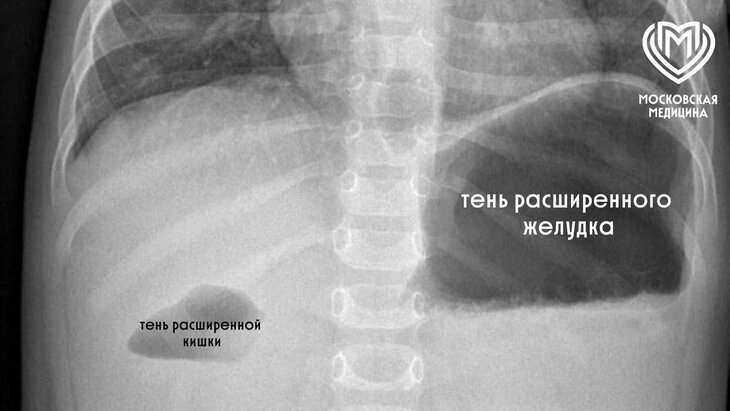

В результате обследования врачи обнаружили, что в 12-перстной кишке маленькой пациентки сформировалась толстая мембрана, которая почти полностью блокировала прохождение пищи.